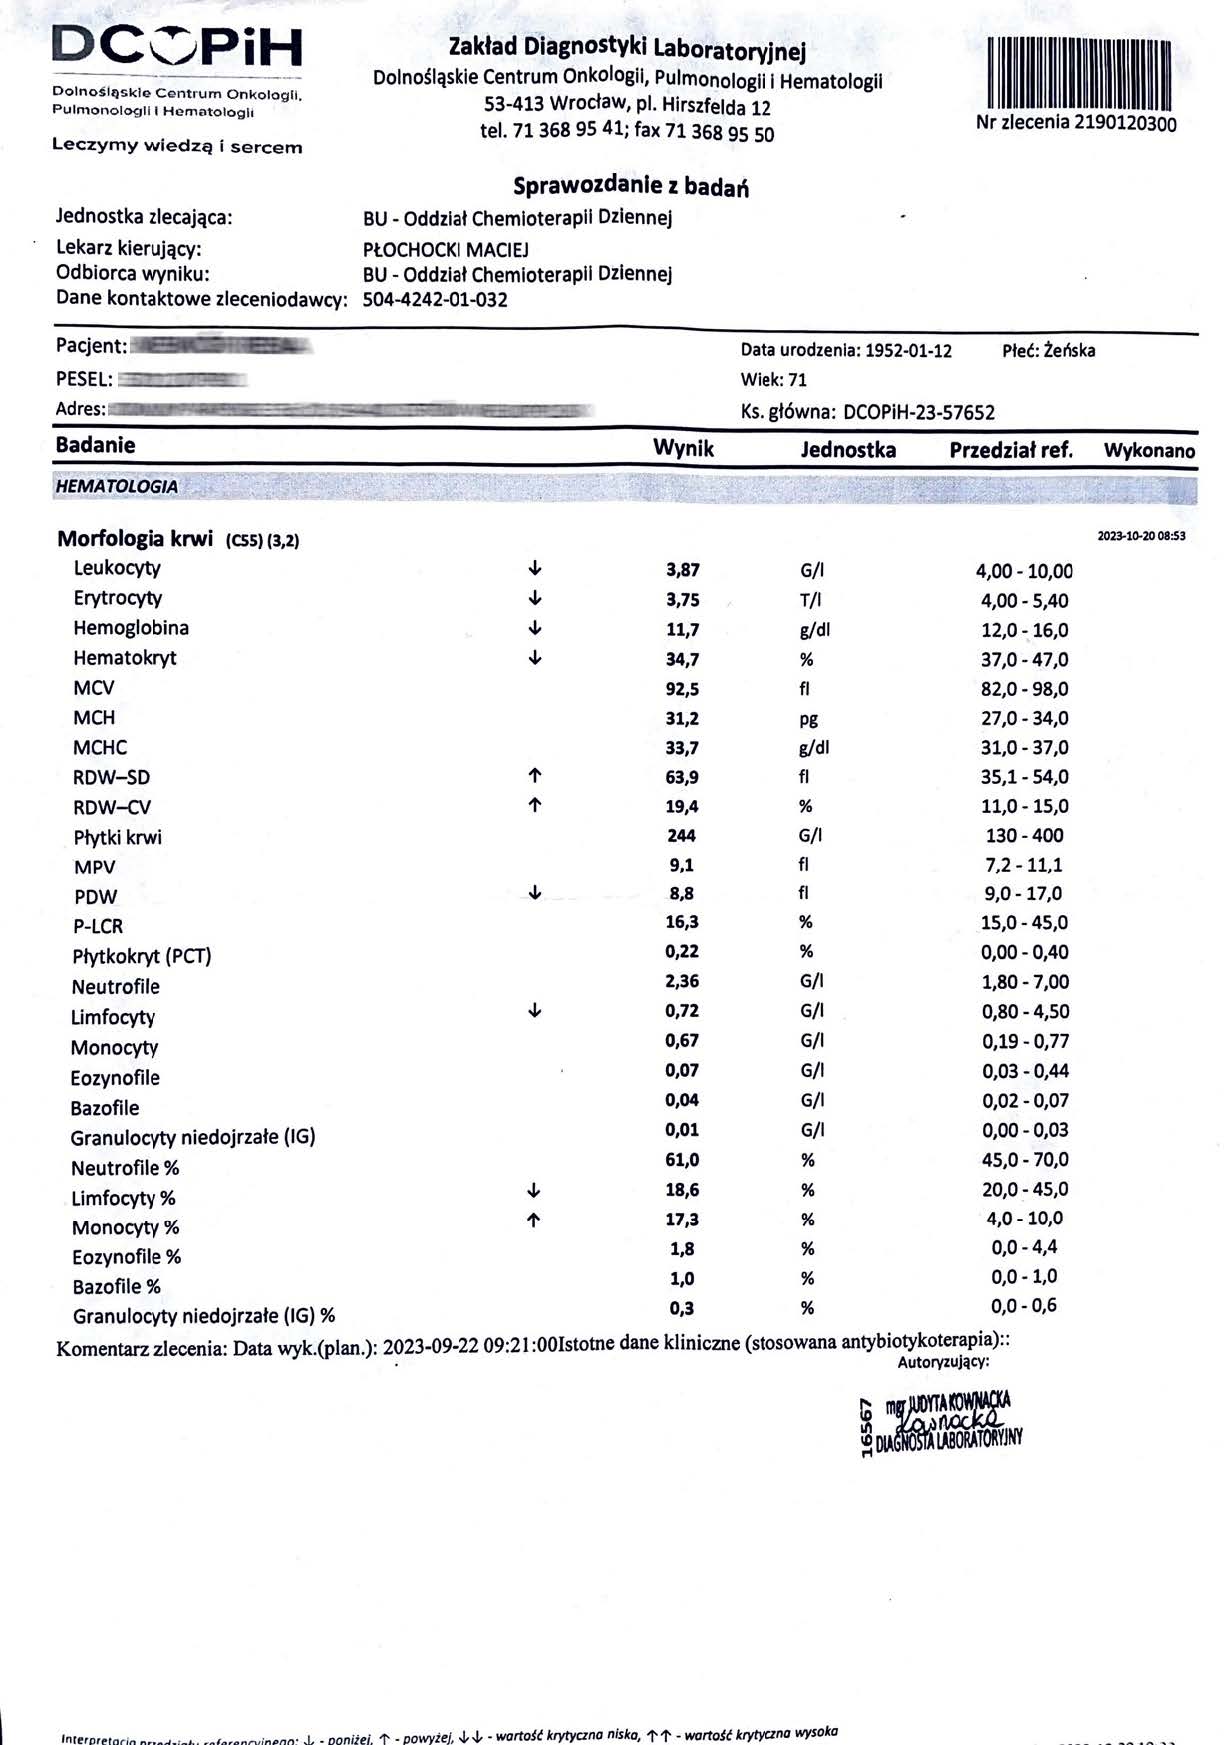

EFEKT PREPARATU NA RAKA PIERSI

Kobieta lat 71, rak piersi w IV stadium, zaawansowane stadium metastazy. W trakcie stosowania preparatu odnotowano spadek markerów Ca 15-3 z wartości 140,0 U/ml do 78,3 U/ml oraz spadek markeru CEA z 11,8 ng/ml do 8,4 ng/ml w zaledwie 3 miesiące, odnotowano stabilność szpiku. Wyniki wykazują zahamowanie progresji, dodatkowo odnotowano cechy uzupełniające terapię farmakologiczną, więc jest to jeden z przykładów wspomagania leczenia systemowego.